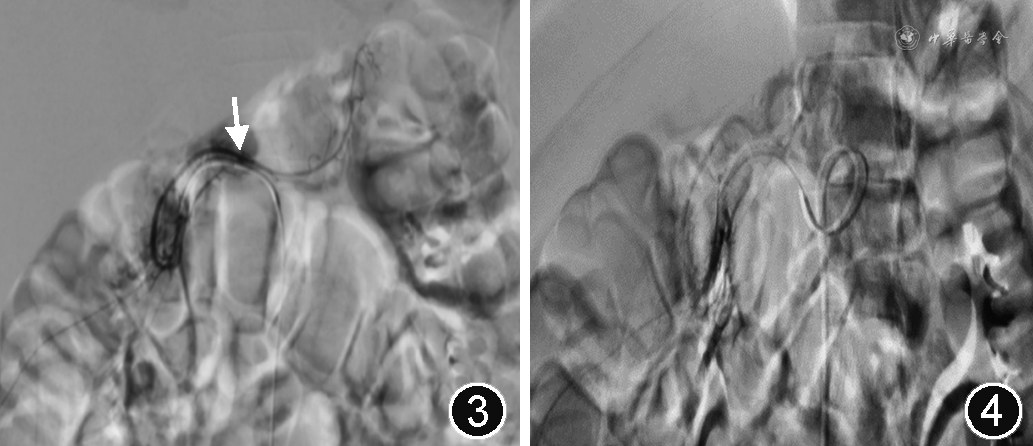

急诊行腹腔干及肠系膜动脉介入造影检查:采用Seldinger技术穿刺右股动脉,导管置于腹腔干动脉,依次行各个分支血管造影检查,发现胃十二指肠动脉远端分支直径较粗且恒定,存在点状造影剂泄露(图3,黄色箭头),诊断为:十二指肠Dieulafoy病变。用超微导丝行出血点血管的1 000~1 400 μm明胶海绵栓塞,复查造影证实栓塞满意(图4)。10 d后患儿顺利出院,出院后门诊随访7个月,未出现便血。